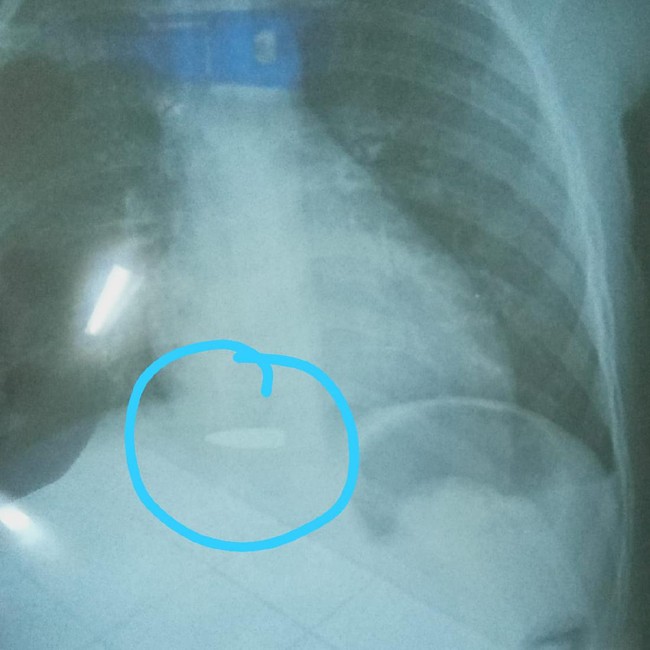

Peluru yang sempat bersarang di tubuh bocah asal Kabupaten Bandung Barat (Foto: Istimewa).

Pada Senin (22/11/2021) peluru yang hampir mengenai bagian tulang belakang Abdul berhasil diangkat. Kini bocah itu selamat namun belum bisa berkomunikasi dan masih menjalani pemulihan.